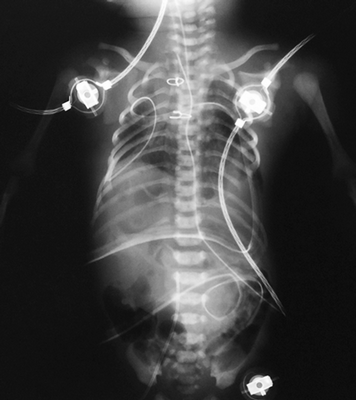

Доношенная девочка переведена в отделение анестезиологии и реанимации кардиохирургии перинатального центра ГБОУ ВО «СПбГПМУ» на 2-е сутки после рождения в Демьянской ЦРБ. В анамнезе: ребенок от вторых срочных самостоятельных родов, ручное отделение последа, седьмой беременности, во время беременности мать на учете не состояла, простудные заболевания в анамнезе. Масса ребенка при рождении 2215 г, рост 44 см. Апгар 7/8 баллов, состояние с рождения тяжелое, неврологическая симптоматика проявлялась гипотонией, гипорефлексией, акроцианозом. С 1-х суток жизни ребенок находился на искусственной вентиляции легких (ИВЛ), с жесткими параметрами, показатели сатурации 95 %. В легких дыхание проводилось с обеих сторон с наличием единичных хрипов проводного характера. Тоны сердца ритмичные. ЧСС — 130/мин. АД 52/25 мм рт. ст. Живот не вздут, мягкий, диурез сохранен. Локально определялся дефект передней грудной и брюшной стенок, в просвете дефекта зияло сердце с омфалоцеле (содержащим, предположительно, желудок), непокрытые кожно-апоневротическим компонентом. Дефект был прикрыт марлевой повязкой, смоченной в подогретом растворе фурацилина. В Демьянской ЦРБ получала лечение: антибиотики ампициллин 50мг/кг 2 раза/сутки внутривенно, инфузионная терапия (глюкоза 10 %, аминовен 10 %) в V = ФП, дицинон, обезболивающие, инотропная поддержка (дофамин 0,5 % 2мкг/кг × мин).

При осмотре новорожденной на момент поступления в кардиохирургического отделения перинатального центра ГБОУ ВО СПбГПМУ выявлены все 5 признаков синдрома, в том числе врожденный порок сердца, заболевание классифицировано как 1-й класс по Тояма (рис. 1).

Рис. 1. Новорожденная девочка, 2-х суток жизни, поступившая с диагнозом врожденная эктопия сердца, омфалоцеле

Ребенок был осмотрен коллегией специалистов: неонатологом, кардиологом, кардиохирургом, торакоабдоминальным хирургом, неврологом. Состояние ребенка расценено как стабильное, тяжелое, сознание на момент осмотра медикаментозно угнетено. При поступлении пациентке выполнена обзорная рентгенограмма грудной и брюшной полостей, визуализирующая сердечную тень в проекции эпигастрия, что дало представление о эвентрации сердца на переднюю брюшную стенку, однако не отражало анатомию внутрисердечных структур. Верхняя доля правого легкого ателектазирована, в дистальных отделах обоих легких выявлены признаки интерстициального отека легочной паренхимы. Контуры диафрагмы четкие, ровные (рис. 2). Учитывая отсутствие возможности проведения трансторакального ЭХО-КГ, в силу отсутствия кожно-апоневротического компонента, покрывающего сердце, в рамках предоперационного планирования принято решение о выполнении мультиспиральной компьютерной томографии (МСКТ) области грудной клетки с целью определения анатомии внутрисердечных структур и определения типа врожденного порока сердца.

Рис. 2. Обзорный ренгтеновский снимок, показывающий атипичную локализацию сердечной тени, асимметричное положение диафрагмы, неравномерную пневматизацию легочной ткани

В раннем послеоперационном периоде состояние ребенка тяжелое, относительно стабильное, обусловлено дыхательной недостаточностью, сердечной недостаточностью, в том числе по причине врожденного порока сердца, объемом и травматичностью хирургического вмешательства. По завершении операции выполнена обзорная рентгенограмма грудной и брюшной полостей, на которой тень сердца расположена в левой половине грудной клетки (рис. 10), в верхних сегментах правого легкого сохраняется гиповентиляция, в остальных отделах легких признаки отека, контуры диафрагмы не четкие, в грудной и брюшной полостях определяются дренажи, в просвете трахеи интубационная трубка.

Рис. 10. Обзорный рентгеновский снимок, 1-е сутки после операции, сердце низведено в левую половину грудной клетки, положение диафрагмы асимметричное, пневматизация легких неравномерная

На фоне инфузии адреналина, милринона, метазона гемодинамика пациента оставалась относительно стабильной. Лабораторно отмечались признаки ацидоза, гиперкапнии. За время наблюдения состояние ребенка ухудшалось преимущественно за счет дыхательной недостаточности, отмечалось нарастание сердечной и печеночной недостаточностей, наблюдалась анурия, несмотря на проводимую стимуляцию лазиксом. Учитывая прогрессивное ухудшение состояния, ребенок переведен на высокочастотную ИВЛ (ВЧ ИВЛ), начат перитонеальный диализ. На фоне ВЧ ИВЛ выполнена обзорная рентгенограмма (рис. 11), пневматизация обоих легких улучшилась, сохраняются признаки отека легочной паренхимы. На 2-е сутки после операции состояние ребенка продолжало прогрессивно ухудшаться, несмотря на продолжающуюся терапию, и расценено как крайне тяжелое. На фоне высокодозной инотропной поддержки гемодинамика продолжала оставаться неустойчивой, отмечалась брадикардия, гипотония. После неоднократно проведенного непрямого массажа сердца, повторного перитонеального диализа на фоне введения максимальных доз иноторопных препаратов наблюдалась асистолия, констатирована клиническая и биологическая смерть пациента.

Рис. 11. Обзорный рентгеновский снимок после проведения ВЧ ИВЛ, пневматизация легочной паренхимы более равномерная